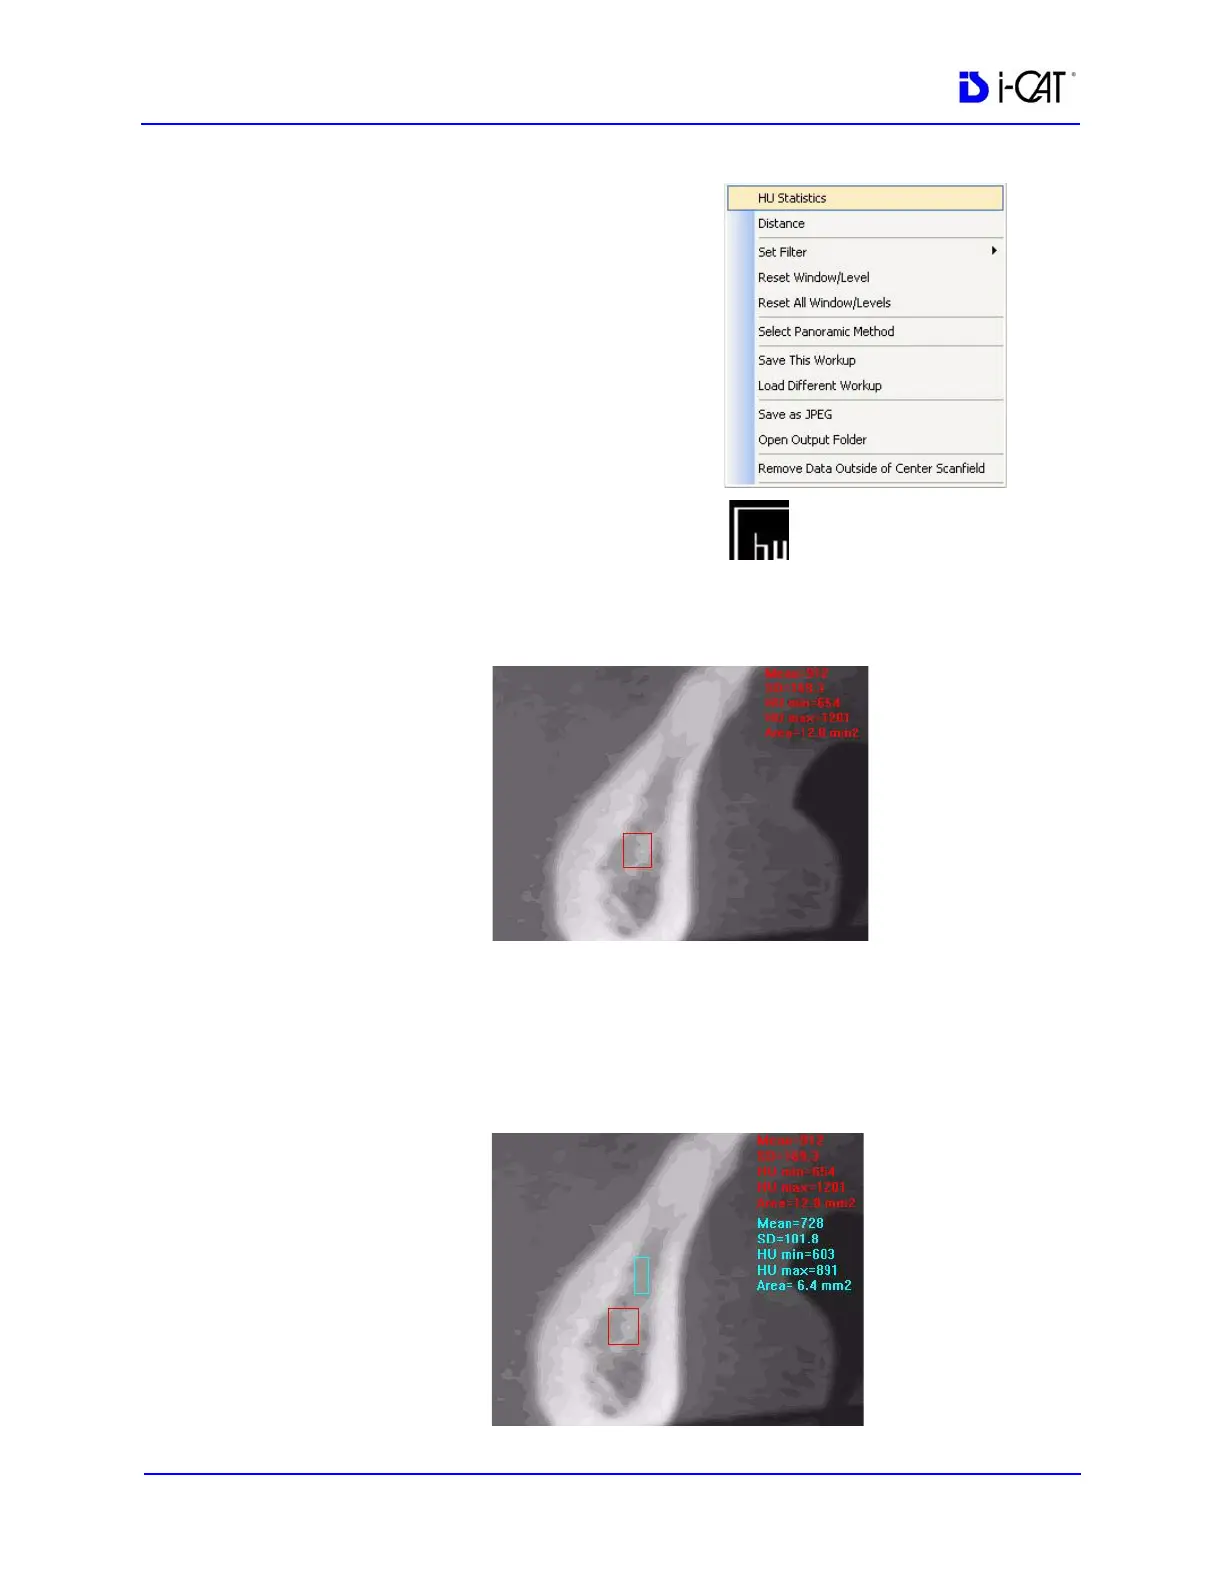

1. To make an HU measurement,

right click image and select HU

Statistics.

The menu closes and the cursor

changes to the hu measurement

symbol.

2. Click, drag, and click to define an area. Measurement statistics

appear in the upper right corner of the image.

3. Repeat steps 2 and 3 to take additional measurements. A

maximum of four HU measurements can be taken at a time in a

normal view and two in a cross section view. Additional

measurements are displayed in varying colors so that they can be

easily associated with the selected image area.